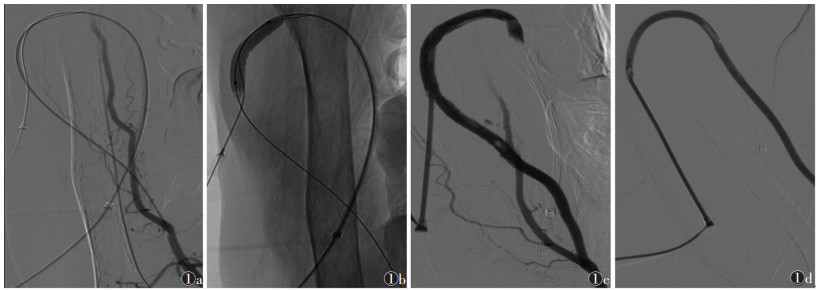

2 结果所有患者经球囊导管碎栓后, 将自人工血管动脉吻合端至静脉侧侧襻介入入口处的血栓经鞘吸出, 而其远端栓子顺血流流入肺动脉内, 均未出现肺栓塞症状(图 1)。经椎管行尿激酶溶栓治疗均未出现穿刺口、脑和肾等出血。血管彩色多普勒超声和(或)造影提示:单发狭窄者15例中, 引流静脉、人工血管、静脉端和动脉端吻合狭窄分别为4、2、7和2例; 2处及其以上狭窄者7例, 其中2处狭窄者6例, 引流静脉与静脉端吻合口、人工血管与动脉端吻合口狭窄分别为4和2例, 另1例出现引流静脉(肱与腋静脉各1处)和静脉端吻合口3处狭窄。22例行PTA治疗后, 19例狭窄率 < 30%, 提示成功; 3例扩张后狭窄率仍>30%, 狭窄位置见表 1。后均成功置入GORE公司的Viabahn覆膜支架。术后当日和次日均使用人工血管行血透治疗。随访6个月, 1例术后36 d因人工血管静脉端吻合口狭窄加重致血栓栓塞, 再次行介入治疗后一直通畅, 余患者血透通路均通畅。

| 图 1 女, 52岁, 1年前因尿毒症行左前臂人工血管动静脉内瘘术, 术后一直采用人工血管行血透治疗 图1a 肱动脉造影示人工血管闭塞 图1b, 1c 经球囊扩张碎栓、鞘抽栓后造影示人工血管动脉段开通 图1d 球囊扩张人工血管静脉吻合口和静脉段闭塞后造影复查示已开通 |